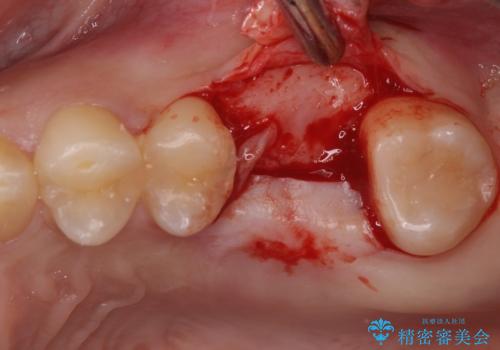

歯列矯正はインビザラインを使用し、矯正治療中の適切な時期に奥歯の欠損部位にインプラントを埋入することとしました。

矯正治療とインプラント治療を同じ歯科医師が担当することで、通常見られるような複数医院を行き来する煩雑さや、複数担当医の見解の違いによる治療の遅滞といった煩わしさは一切なく、スムーズに治療を進めることができました。

- 外科手術のため、術後に痛みや腫れ、違和感を伴います